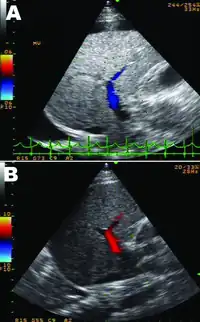

| A person with massive ascites and caput medusae due to cirrhotic liver failure | |